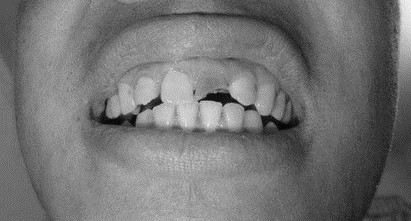

患者,男,38歲。上前牙變色1年,自述上前牙5年前受過外傷,唇側(cè)傾斜,檢查可見左上1牙冠變色,牙冠缺損近1/2,牙髓測試無反應(yīng),X線根尖片顯示患牙無明顯異常,全景片顯示雙側(cè)下頜智齒近中阻生,之前有發(fā)炎化膿病史,目前無咀嚼不適??谇黄溆酂o異常。

檢查情況及X線片見下圖:

病例分析2

(1)下前牙變色1年,下前牙5年前受過外傷,唇傾明顯。

(2)檢查見左上1牙冠變色,牙髓測試無反應(yīng),牙冠缺損近1/2,X線片無明顯異常。